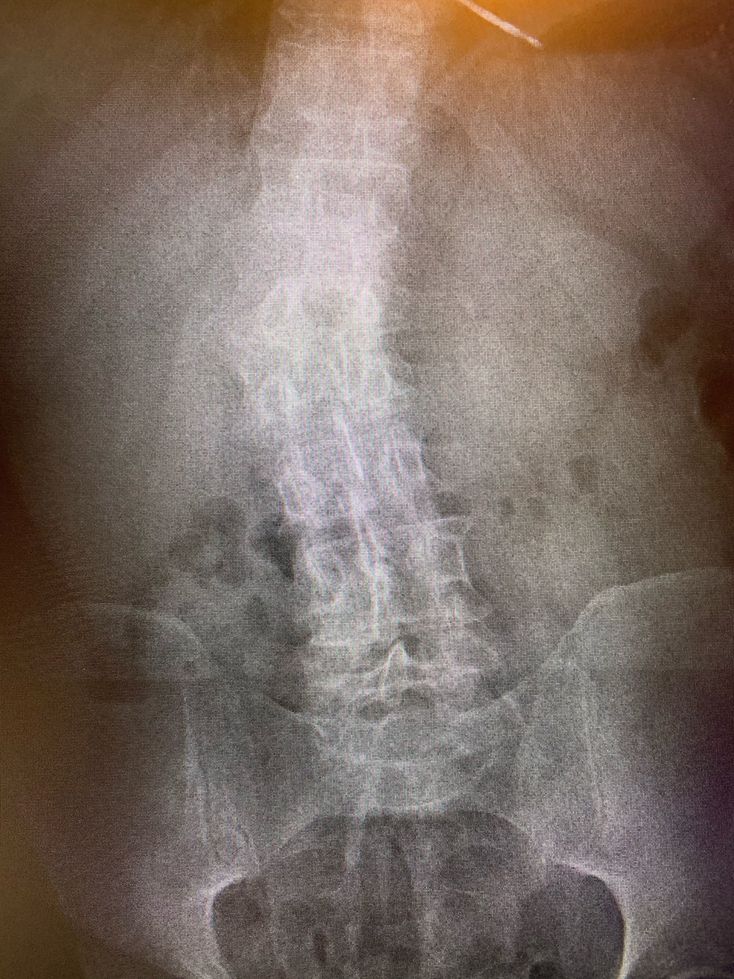

What went wrong ??

Xray

Scoliosis

Vertebral column is not straight-scoliosis??..